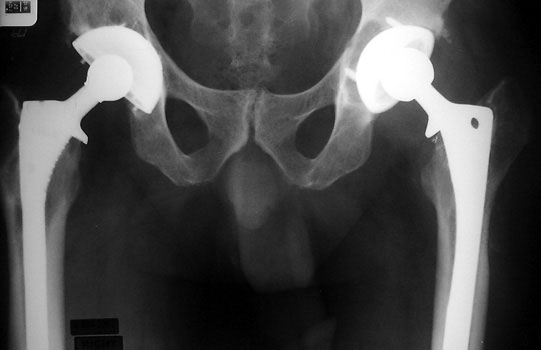

• Cup should be anteverted 15 +/- 10 degrees.

• Anteversion is difficult to accurately evaluate on radiographs, and can only be qualitatively assessed on a groin lateral view. This view is difficult to obtain, especially in the elderly or post operative patient, and is effected by pelvic or thigh rotation.

• CT is the imaging modality of choice to evaluate for anteversion

The right cup is normally anteverted, the left cup anterior and posterior rims are far apart, suggesting excessive anteversion.

R

L

Groin lateral films: R cup normal anteversion, L cup excessive anteversion